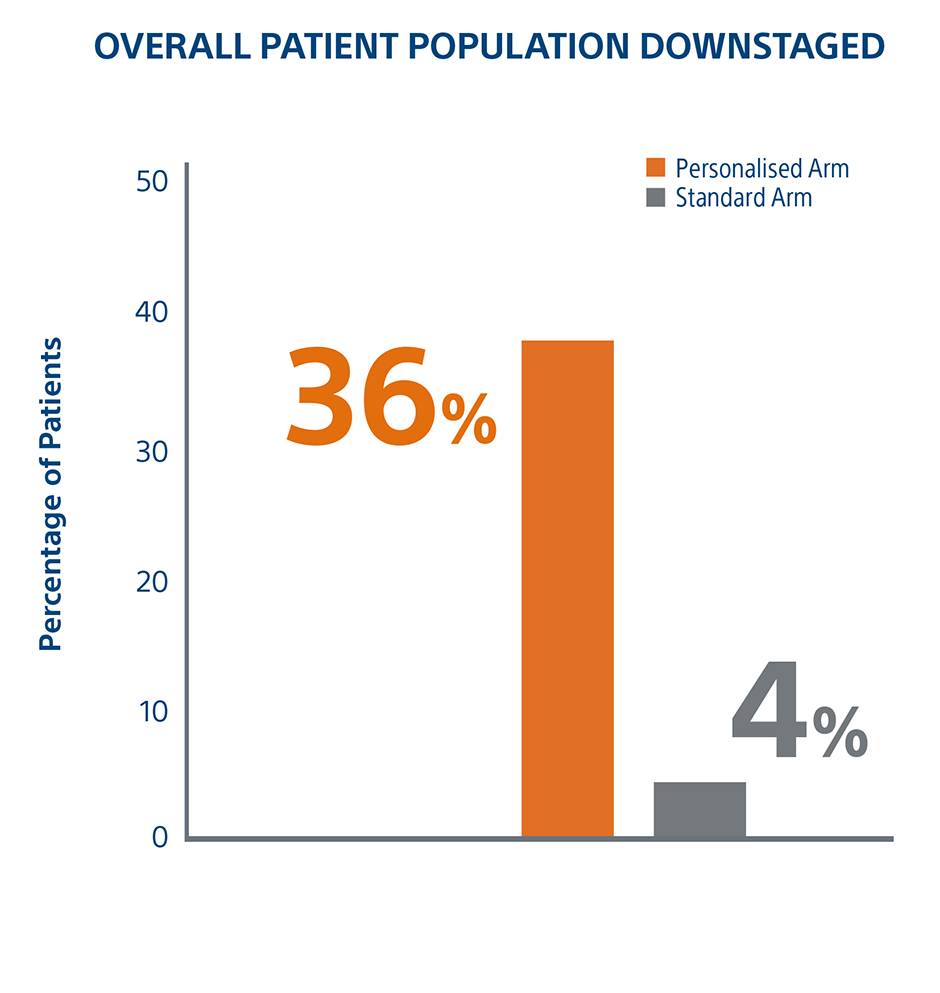

Personalized Dosimetry Downstages More Patients To Surgery